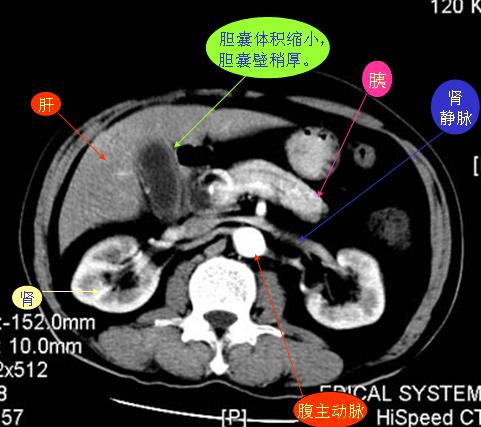

腹部ct解剖与基本病变